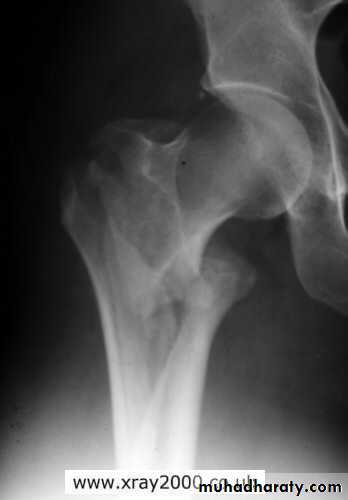

Inter-trochanteric fractures (extracapsular fracture)

.It is extra capsular fracture occurs in elderly.

.Unite quite easily and seldom cause a vascular necrosis.

The crack runs up between the lesser and greater trochanter.

Pathological anatomy divided into:

Stable:

Unstable are those where

a. posteriomedial cortex is shattered.

b. poor contact between fracture segment.